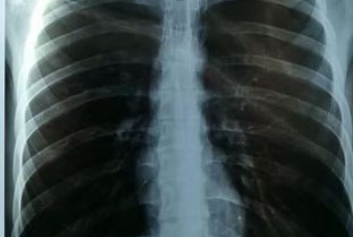

去医院做 CT、核磁共振检查后,你是否好奇:那些黑白影像如何变成诊断依据?医生又如何快速调取几年前的检查报告?答案藏在一个看不见却至关重要的医疗大脑里 ——医学影像 PACS 系统。跟着超声工作站/云胶片迈德卫医疗影像云一起来了解下吧!在没有 PACS 的年代...

在医疗影像领域,胶片不仅是病情记录的载体,更是医生精准诊断的第二双眼睛。而市面上主流的激光胶片与热敏胶片,看似功能相近,实则在核心性能上有着天壤之别。今天就让我们跟着远程超声/影像云迈德卫医疗来拆解两者的关键差异。激光胶片的成像逻辑如同 “精准光绘”&...